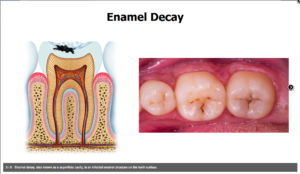

صورة ٢. تسوس طبقة المينا

بعد ذلك يحدث تآكل في طبقة “المينا” في السن مما يؤدي إلى حدوث ثقوب صغيرة فيها

الشخص الذي يعاني من تسوس الأسنان قد لا يكون على علم بالمرض. أول مؤشر على الآفات التسوسية الجديدة هي ظهور البقع البيضاء و البنية على سطح الأسنان، مما يشير إلى منطقة الهجوم على المينا